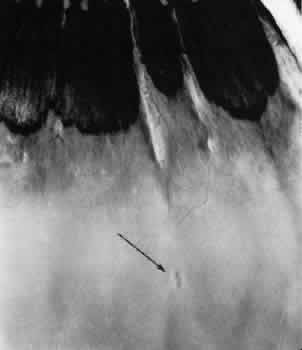

Most retinal holes (76%) are secondary to lattice degeneration.20 Primary retinal holes, unrelated to lattice degeneration or other identifiable disorders, are rounded, full-thickness retinal breaks without a flap or a free operculum (Fig. 27). Usually located anteriorly within the area of the vitreous base, the holes have smooth margins; the adjacent retina usually appears normal; proliferative reactions are absent; and vitreous attachments are not unusual.11

Fig. 27. Retinal hole with round, full-thickness break immediately behind the ora serrata in an area of relatively normal retina. Typical cystoid degeneration extensively involves retina on both sides of retinal hole. (× 16.)

Microsections of retinal holes confirm the complete retinal discontinuity and the smooth, rounded margins (Fig. 28). There is minimal reactive gliosis; no significant alteration is found in the adjacent vitreous body or in the pigment epithelium.

Fig. 28. Full-thickness retinal break in otherwise normal-appearing peripheral retina. Outer retinal layers are intact. (Hematoxylin-eosin; × 250.)

Primary retinal holes are present in 7.5% of adults, they are bilateral in 21% of patients, and thus are evident in 12% of adult eyes (see Table 3). Virtually all retinal holes occur within the vitreous base and give no evidence of quadrant predilection.

Retinal holes are detected clinically by indirect ophthalmoscopy and by contact lens biomicroscopy. Scleral depression is helpful in differentiating a retinal hole from a round retinal hemorrhage: the retinal hole develops a changing reddish color as it moves over the crest of the scleral depression, and the round retinal hemorrhage maintains a stable red color as it moves over the crest of the scleral depression. Asymptomatic round retinal holes with or without free opercula do not generally require treatment. A rhegmatogenous retinal detachment rarely originates from an untreated retinal hole.21 However, retinal holes located within a rhegmatogenous retinal detachment should be treated during the surgical repair as these can be a source of persistent subretinal fluid postoperatively.